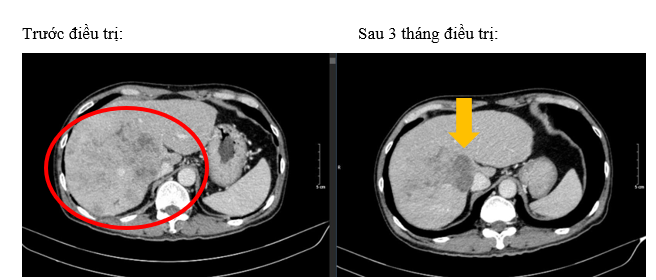

Hình 1. Hình ảnh khối nốt nhu mô gan hai bên lan tỏa (vòng tròn đỏ) – tính chất HCC, xâm lấn gây huyết khối các nhánh phải và thân chung tĩnh mạch cửa

Hình 4. So sánh kích thước và hình thái khối u trước điều trị (vòng tròn đỏ) và sau điều trị 3 tháng (mũi tên vàng).

- Bệnh nhân đạt đáp ứng tốt với điều trị: khối u thu nhỏ kích thước đáng kể, lâm sàng được cải thiện rõ rệt. Trong quá trình điều trị, bệnh nhân có xuất hiện một số tác dụng phụ như: mệt mỏi, hội chứng bàn tay bàn chân mức độ nhẹ. Ngoài ra bệnh nhân không gặp tác dụng phụ khác.

Đánh giá theo tiêu chuẩn mRECIST 1.1, bệnh đáp ứng một phần (PR – Partial Responce). Hiện tại, bệnh nhân tiếp tục được điều trị với lenvatinib liều 8mg/ngày.